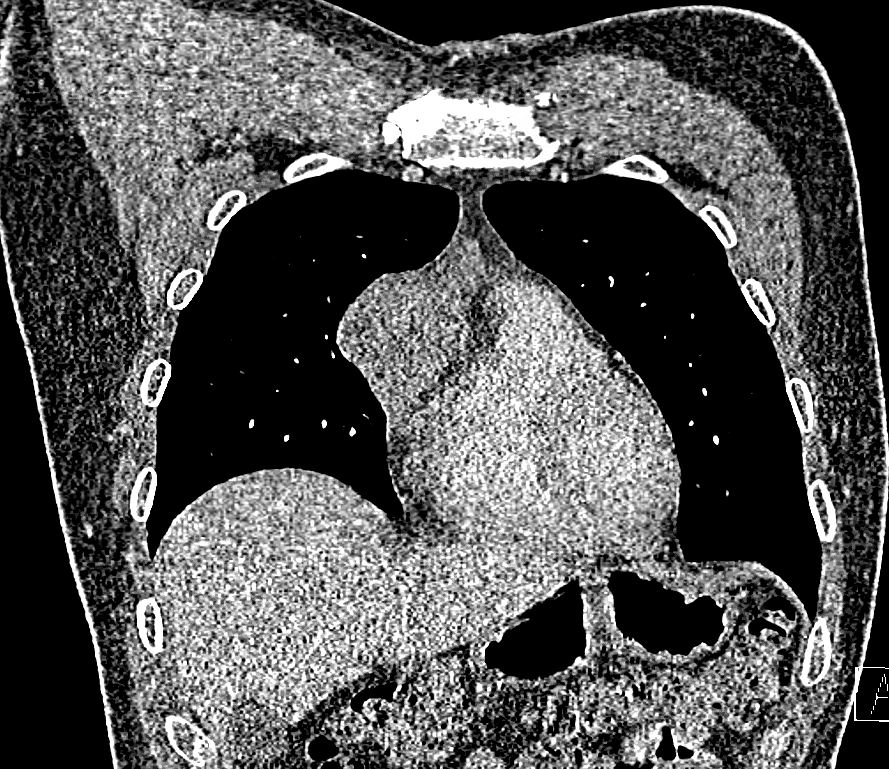

It was by sheer coincidence that the Emirati man recently discovered a 7cm tumour in his chest following a medical examination.

“They start off as a benign growth related to immune disease and sometimes change to malignant tumours. These malignant thymoma tumours grow slowly and eventually encase the lung and heart as well as spread around the patient's body. For this patient, it had not spread beyond the tumour mass. But yes, it is a serious disease.”

Talking about the initial diagnosis, Dr Black said: “This tumour was part of an immune problem of the thymus gland in the chest. This was producing antibodies that affect the ability of nerves to activate muscles, so the symptoms are generalised fatigue that gets worse each day, better after sleep and so on.”

“Recurrence is a risk for malignant thymomas, especially the large ones, which is why we provide prophylactic radiotherapy. Recurrence can be very late as these tumours grow slowly so CT scan of his chest will be offered at post operation 1 year, 2 years then every 2 years after that.”